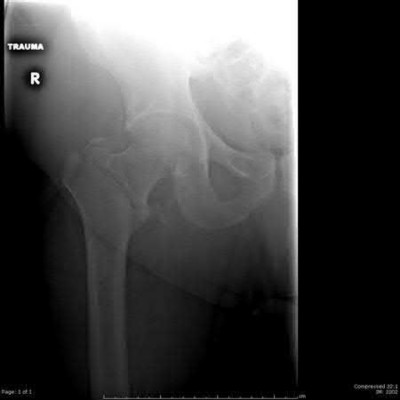

A 12-year-old boy with a BMI in the 98th percentile presents with 3 weeks of vague left groin and knee pain. He walks with an antalgic, externally rotated gait. Radiographs confirm a stable left slipped capital femoral epiphysis (SCFE). Which of the following is the strongest indication for prophylactic in situ pinning of his asymptomatic right hip?

Options:

- Age greater than 14 years at initial presentation

- Posterior sloping angle of 40 degrees on the affected side

- Concomitant diagnosis of hypothyroidism

- Unilateral slip angle greater than 60 degrees

- BMI greater than the 95th percentile

Correct Answer: Concomitant diagnosis of hypothyroidism

Explanation:

Endocrine disorders (such as hypothyroidism, panhypopituitarism, or renal osteodystrophy) and previous radiation therapy are strong indications for prophylactic contralateral pinning in SCFE due to the exceptionally high risk of a subsequent contralateral slip. While young age (e.g., < 10 years) and open triradiate cartilage are also considered risk factors for contralateral disease, a high BMI alone or the severity of the unilateral slip does not represent an absolute indication for prophylactic pinning.